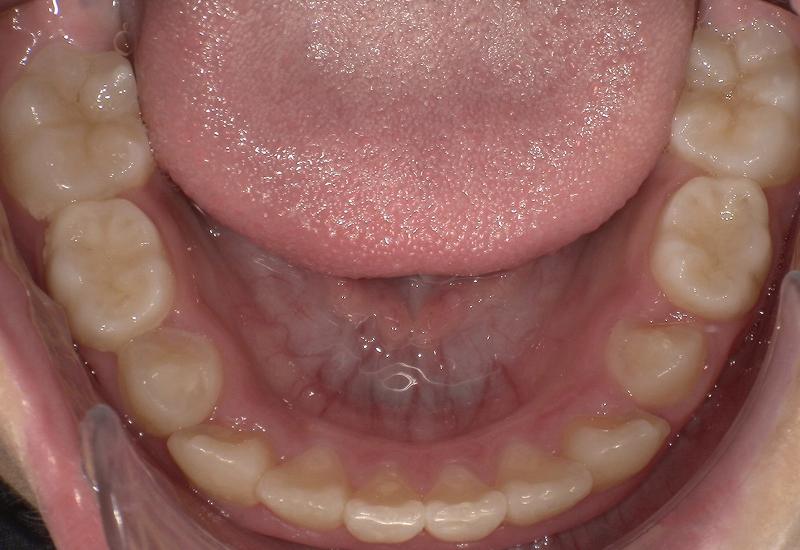

症例② シェイプメモリーアライナーによる混合歯列期の矯正

治療期間 6ヶ月

治療時の年齢/性別 10歳 / 女性

かかった治療費 440,000円

治療方法 シェイプメモリーアライナー

注意点・リスク 今、現在萌えてきている永久歯を動かす為、なるべく早く治療を終了させる